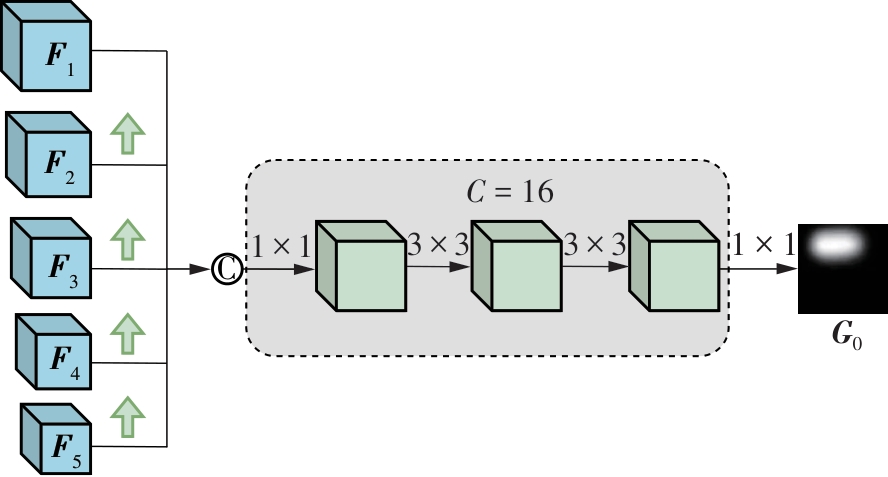

乳腺癌是全球女性最常见的恶性肿瘤之一,准确的病变分割对于乳腺癌的早期诊断与治疗具有重要意义。然而,由于病变形态的多样性以及超声成像机制的复杂性,现有基于深度学习的乳腺超声图像病变分割方法在分割准确性方面仍面临巨大挑战。为进一步提升乳腺超声图像中病变区域的分割精度,该文基于经典U-Net架构,提出了一种新型乳腺超声图像病变分割网络(CWSASKM-BBAM-Net)。首先,在网络中引入逐通道空间自适应选择核卷积模块(CWSASKM),根据不同通道的语义特征为每个空间位置自适应选择感受野大小,以增强多尺度信息的建模能力;然后,引入双向边界感知机制(BBAM),通过融合正向与反向注意力,对目标显著区域及其边界进行协同建模,同时逐步提升对非显著区域与病变区域的区分能力,以进一步强化边界信息的表达;最后,在3组公开乳腺超声图像数据集(BUSI、UDIAT和STU)上开展分割实验。结果表明:该方法在数据集BUSI上的杰卡德指数、精确率、召回率和Dice相似系数分别为71.97%、82.85%、81.40%和80.44%,较次优方法分别提升1.69、1.05、1.28和1.84个百分点;在数据集UDIAT上,这4项指标分别达到78.14%、88.31%、86.73%和86.10%,较次优方法分别提升了2.75、2.04、0.56和2.01个百分点;在外部数据集STU上,该方法也取得了优于其他方法的整体表现。实验结果表明,CWSASKM-BBAM-Net在乳腺超声图像分割任务中展现出更优的整体性能。